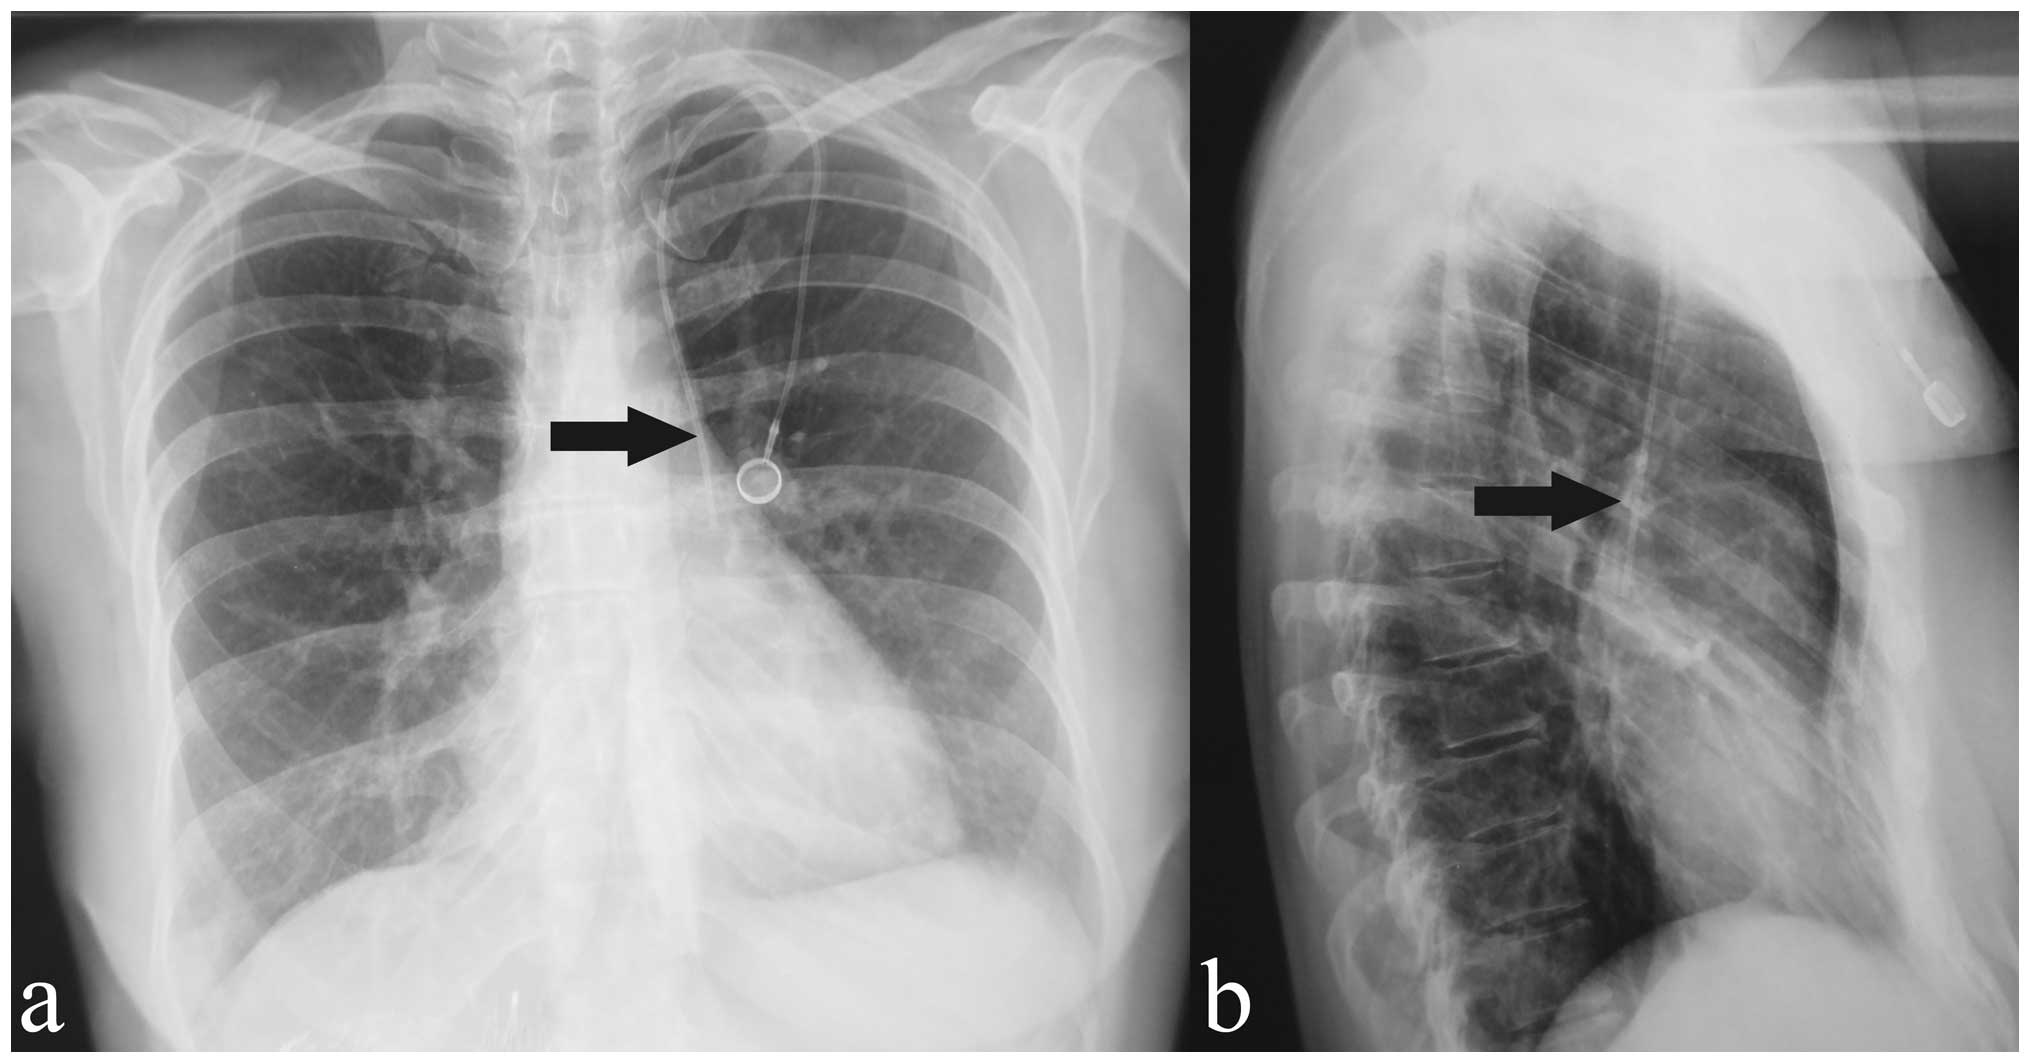

This is how the lungs look on CT – the most effective method for diagnosing lung cancer

Often in patients with these symptoms on X-rays or CT scans, we see a large tumor with in-growth into large blood vessels or we detect metastases in other organs.

Hemoptysis can be associated not only with lung cancer, this symptom can occur with pulmonary tuberculosis and some other diseases. In the photo: the black area is the lungs, the white spots are pneumonia. Moreover, in patients with the first stage, the five-year survival rate reaches 80% after the operation. In the second and third stages, the situation is more complicated: the second we can start with a surgical method, but most often postoperative chemotherapy will be required.